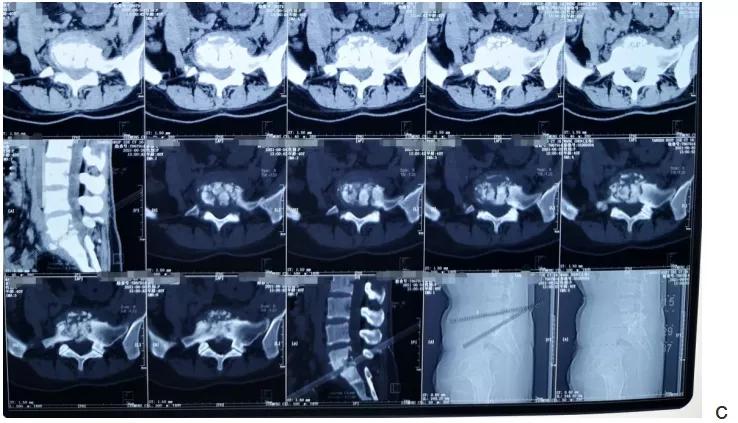

术前影像学表现

d.MR显示椎体和椎间隙不均质高信号改变,椎体两旁和相应椎管内可见不均质高信号影,为脓肿形成,椎管受压。